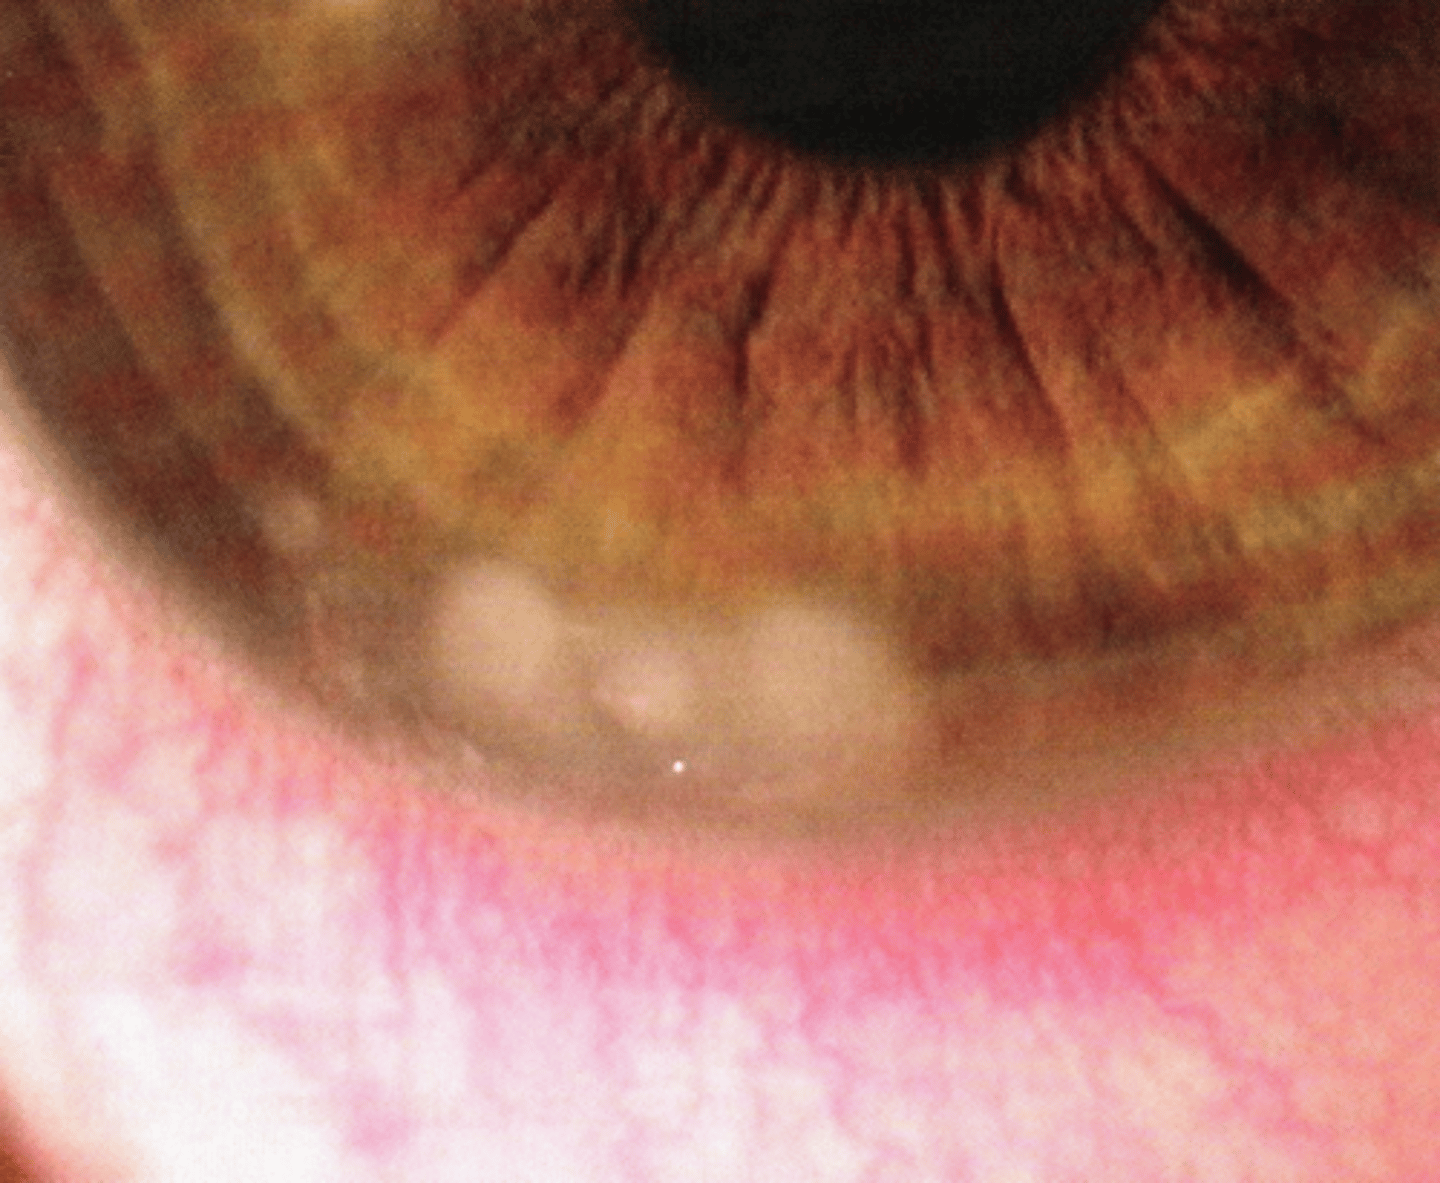

chalazion

What condition shown here must we consider with a hordeolum?

localized bumb of coagulated lipid within meibomian gland (NOT an active infection)

What is a chalazion?

hard nodule, NOT warm to touch, NOT red

What presentation differentiates a chalazion from an internal hordeoolum?